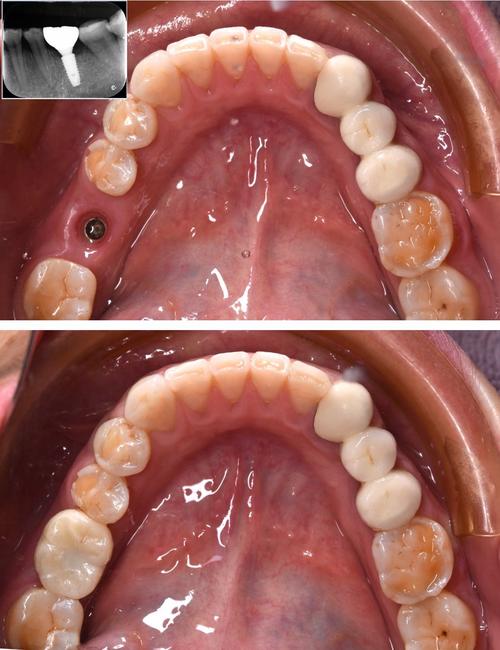

种植牙的成功,离不开精准的影像检查,现代口腔种植常用的影像技术包括根尖片、曲面断层片及锥形束CT(CBCT),其中CBCT因三维成像、高分辨率、辐射剂量可控等优势,已成为种植术前的“金标准”,拍片的核心作用体现在以下方面:

精确测量骨量,制定安全植入方案

CBCT可三维重建牙槽骨形态,清晰显示骨的高度、宽度、密度,以及骨内凹陷、缺损区域,医生通过软件分析,可精确计算种植体的直径、长度,选择合适的种植体型号,确保种植体植入后周围有至少1-2mm的骨壁包裹,提供初期稳定性,对于牙槽骨严重萎缩的患者,可通过CBCT判断是否需要植骨、骨增量手术的量及范围,避免盲目种植。

定位重要解剖结构,规避手术风险

CBCT能清晰显示下牙槽神经管、上颌窦底、颏孔、鼻腭管等解剖结构的位置及走行,下颌后牙区的种植体需距离下牙槽神经管至少2mm,上颌后牙区的种植体需距离上颌窦底至少1mm,CBCT可帮助医生精准标记安全植入范围,避免神经损伤和上颌窦穿孔,对于邻牙牙根倾斜、弯曲的情况,CBCT可明确牙根形态,确保种植体与牙根间保持足够距离(至少1.5mm)。